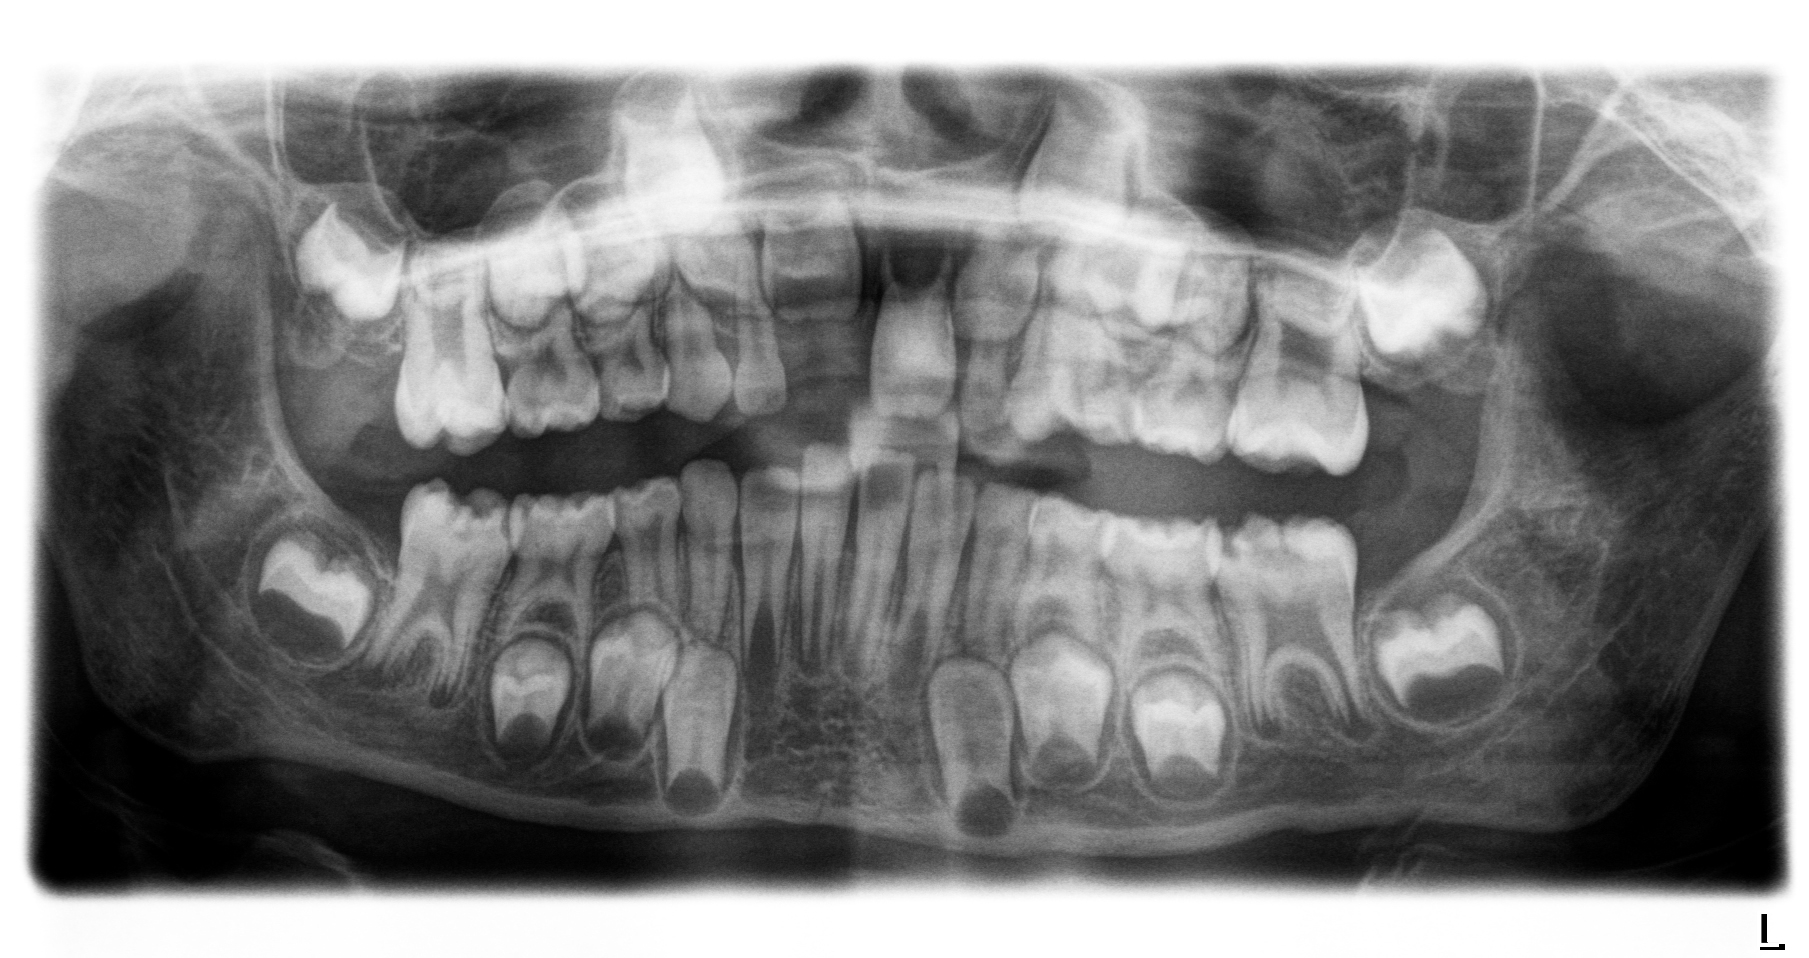

Diese Klassifikation dient als Grundlage für die Therapieempfehlungen. Deutlich wird, dass aufgrund der Symptomatik die Therapie der Zähne höchst unterschiedlich ausfällt. Dass etwa eine Opazität ohne Überempfindlichkeit (Index 1, Abbildung 1) ein anderes therapeutisches Vorgehen erfordert als ein Zahn mit nahezu komplettem Einbruch der Zahnoberfläche und mit Hypersensitivität (Index 4, Abbildung 2), ist offensichtlich.

Die temporäre Therapie C (kurzfristig)

Die Therapie C hat das Ziel, MIH-Zähne vorübergehend zu versorgen, bis der vollständige Durchbruch der Zähne eine adhäsive Restauration ermöglicht, um die hypersensiblen Zähne zu desensibilisieren oder/und die Mitarbeit für die weitere Behandlung aufzubauen. Vor dem Hintergrund des erhöhten Kariesrisikos dieser Zähne (Abbildung 2) muss durch die Maßnahmen eine Kariesprogression vermieden werden.